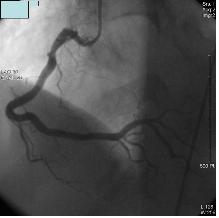

#. ɱ̶ٰ ?

- ⱸ 뵿ƿ ̶ ϸ (ɱ) ȴ. ¸ Ȱ ϱ Ͽ ȯŰ ü ̳ ҳ Ҹ ƾ ϹǷ װ ſ ߿ϴ. ο ǰ ϰ Ǹ ɱ ¿ ̸ Ǵµ ̷ ȯ ̶ Ѵ.

ƿ ưȭ ǰ ̿ Ͽ ü, ưȭ öũ Ŀ̳ ־ Ϻΰ , ɱټ ܵǾ ( ) Ű ɱ̶ٰ մϴ. ۺ а, 帶 縦 ʷ ɼ ϴ. ȯ ȯ 50-70% ź ϰ ִ ȭǾ ̰, 15-20% ϴ ִµ ̴ ַ 索 ȯڳ , ε Ÿ ִ.

#. ɱٰ ? - 漺 Ǵ ȭ̴, ߸ ̷ ħ ϰ ǰ ӵǸ ڲ Ǯ ó ϴ ħ ܴ Į ȴ. ̷ ǰ ɱٿ Ǵ Ͽ, 䱸 Ȳ Ұ ɱ Ÿ ȴ.

ɱ , ִ ưȭ ջ ް ǰ ӿ ִ ǰ ̿ پ Ƕ̶ Ҹ ϰ Ǹ ɱ װ Ǿ ɱ 翡 ̸ ȴ.

ɱٰ Ǵ ưȭ ݵǴµ, ӵ ־ , , , 索 ȴ. , , ݷ ưȭ 3 ڶ ϸ ̷ 3 ̿ܿ ռ 索, , , Ʈ ưȭ Ų.

ۿ ü ̳, ƿ, 뵿 Ǹ ȯ ȯ ִ.

#. ɱٰ

- ũ Ҿ 2 ִ. 쿡 հ Ѱ Ȥ ȣϴ 찡 ȯڴ ̰ йϴ 谨, ̴ , ſ, , ¥ , Į Ȥ , ǥѴ. Ȥ , , , , , ް ĵǸ, δ ȣ, Ƿΰ, , ǽ ȣϴ 쵵 ִ. ̷ Ȱ üȰ, , Ļ , ۽ ( ҿ ߿ ̵ ), 踦 ǿ ƹڼ ϰų л 쿡 Ÿ ȴ. ̶ Ÿ Ͻ(2-15)̾ ϸ 3-5 , Ʈα۸ ϸ 밳 1 ̳ ɴ´. 20 30 ̻ ӵǴ , ӽð 5 ̳̰ų, ȣ , ϴ , ҵǴ , ̳ ҵǴ , 2cm , ؾ ̴. Ҿ ı ϳ ɱٰ ̿ ġѴ. ɱٰ ȯ 30-60% Կ Ҿ Ѵ. ÿ ϰ, ӵǰų Ƚ Ʈα۸ ϴ 츦 Ѵ.

ٸ ִµ ̴ Ȥ ̸ ħ ȣϰ ǰ Ʈα۸ Į .

ɱٰ ϳ 30 ̻ ξ Ÿµ, ̸鼭 ϰ Ÿ Ǵ ٰ ϸ ġ ϴ Ȳ ǥȴ. Ȱ üȰ, , Ļ , ۽ ( ҿ ߿ ̵ ), 踦 ǿ ƹڼ ϰų л 쿡 Ÿ Ǹ ӽð 30 ̻ ӵȴ. ̶ Ʈα۸ ؿ ־Ƶ ʴ´. ̳ , ̱ Ͽ ǰ ʿϴ. Ư 索 ΰ ִ ȯڿ ߺϱ ϹǷ ʾ 찡 .

ɱٰ ȯ 밳 ܰ ġḦ Ѵ. ϴ ݺǸ Ǹ ã ϰ ˻縦 ƾ Ѵ. ⺻ ˻δ ݷ ˻, ɱȿ ˻ ִ. Ư ̵ ˻縦 ı ϴ ſ ߿ϴ. Ҿ ɱȿ ġ ST δٸ ST ɱٰ ﰢ ʿϴ. ɱȿ ġ ST ST ɱٰ̳ Ҿ ﰢ Կ ġᰡ ݵ ʿϴ.

ǽɵ ˻, 24ð Holter ˻, (Ȥ ) ˻, ˻ ̿Ͽ ϰ ȴ. ֱٿ CT˻縦 3 ̰ ִ.

- CT -

Ȯ ˻ Ÿ Ȥ ȸ ̿Ͽ úα ġŰ Ͽ , Ȯϴ ̴.

- -

#. ɱٰ ġ - ȯ ġῡ , Ϲݿ, , ü ִ. ưȭ ų ִ ġῡ ݵ ݵǾ Ѵ. Բ ǥ ü ϵ ϰ, ڴ ݵ 踦 Ѵ. ΰ Ͽ 帶 30-40 ˷ ִ. . 索. ̵ ȯ ġ ȯ ġ 濡 ſ ߿ϴ. ݷ δ ¡, Ұ, , , 븥, , ǥ̸ ̵ 븦 ϰ Ĺ⸧ , , ⸧ ȭ 븦 ø ٶϴ.

Ϲ . ù°, ü Ȱ ϸ ־ ȯڰ Ҿ ϹǷ Ͽ ϵ Ѵ. ħ. ȭ Ƿ ħ̳ Ļ Ŀ ӵ ٵ, 2ð ̻ ¿ Ѵ.

δ 꿰, Ÿ-Ƶ巹 ü , Į, ƽǸ ִ. ﰢ ʿ ɱٰ ִ. ð ߿ѵ 2ð 3ð ̳ ȿ ݵ ݱ ִ Ȯϰ ϴ ߿ϴ.

üġ Ÿ Ȥ ո Ͽ dz dz Ȯ κ а ϴ Ȯ (Ʈ) ־ ְ ϴ Ʈ Լ Ѵ. ̴ Ͽ ϴ ġῡ 밡 ʿ 밳 üð 1~2ð ̸̳ Ư ݼӸ ߵ ġ ſ ֱ θ Ǵ ġ̴.

üġ ذ ȯ Ͽ ų ̽ϴ ƿȸ ؾ Ѵ.

ȯ ġĢ 캸 켱 ġḦ ϰ Ȯ˻ ߰ߵ ݼӸ Լ Ѵ. ı ϰ Ȯ ؾ ϸ Ư ɱٰ ִ Ȥ Ȯ ݼӸ Լ Ѿ Ѵ.